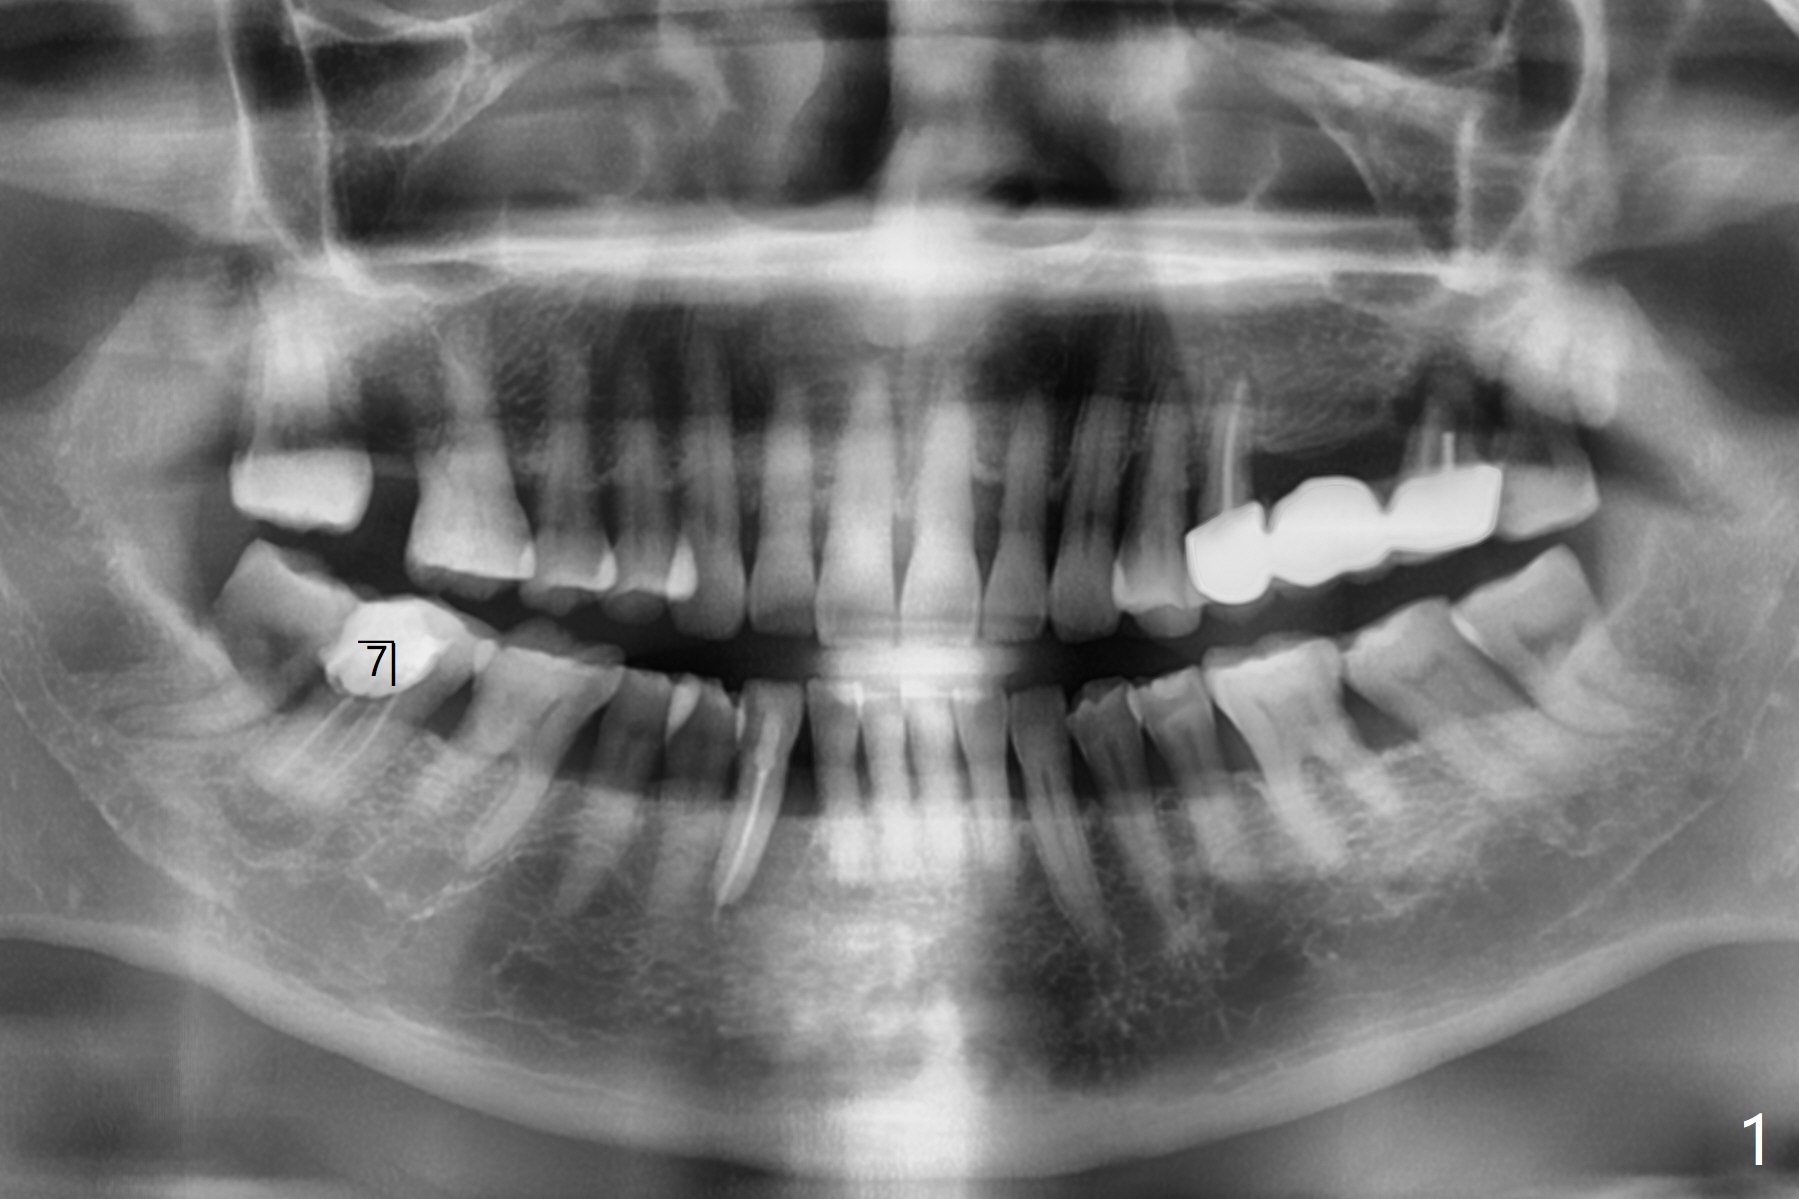

65岁女右下7远中舌侧龈下龋坏(图一,二),远中骨质吸收严重,植体应植入近中窝(图三:绿色),远中窝根部放置胶原塞(蓝色),冠部粘性骨粉(红色)。洁治邻牙,智齿近中面涂Endogain。